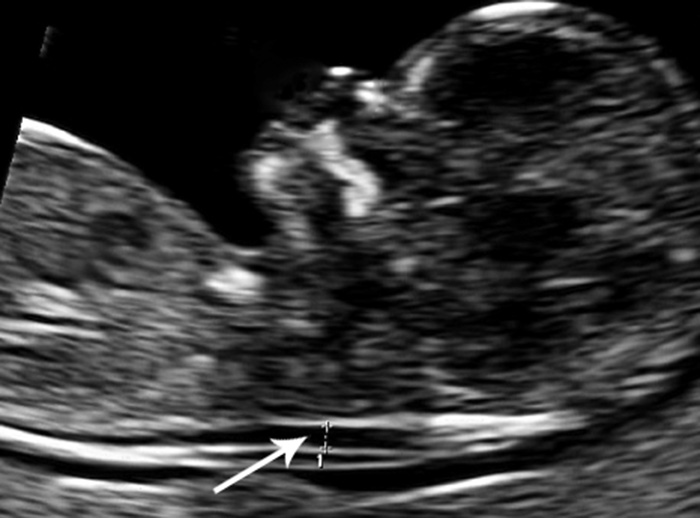

Ultralyd i uke 11 – 13 med måling av nakkeoppklaring (fig 1) og kombinert ultralyd og blodprøve (KUB-test) regnes som fosterdiagnostiske undersøkelser. Nakkeoppklaringen skyldes ødem i nakken hos fosteret, og blodprøvene som tas av mor og inngår i KUB-testen måler konsentrasjonen av humant choriongonadotropin (HCG) og svangerskapsrelatert plasmaprotein A (pregnancy-associated plasma protein A, PAPP-A). KUB-test predikerer sannsynligheten for kromosomavvik eller utviklingsavvik hos fosteret (4) – (6), og metoden ble innført for å unngå komplikasjoner knyttet til invasiv prøvetaking (7). Når ultralydundersøkelser utføres med mistanke om genetisk sykdom, skal det først gis genetisk veiledning. Ultralydundersøkelser i den alminnelige svangerskapsomsorgen, dvs. rutineundersøkelsen i andre trimester og undersøkelser på medisinske indikasjoner, anses ikke som fosterdiagnostikk og omfattes ikke av loven (1, 2).